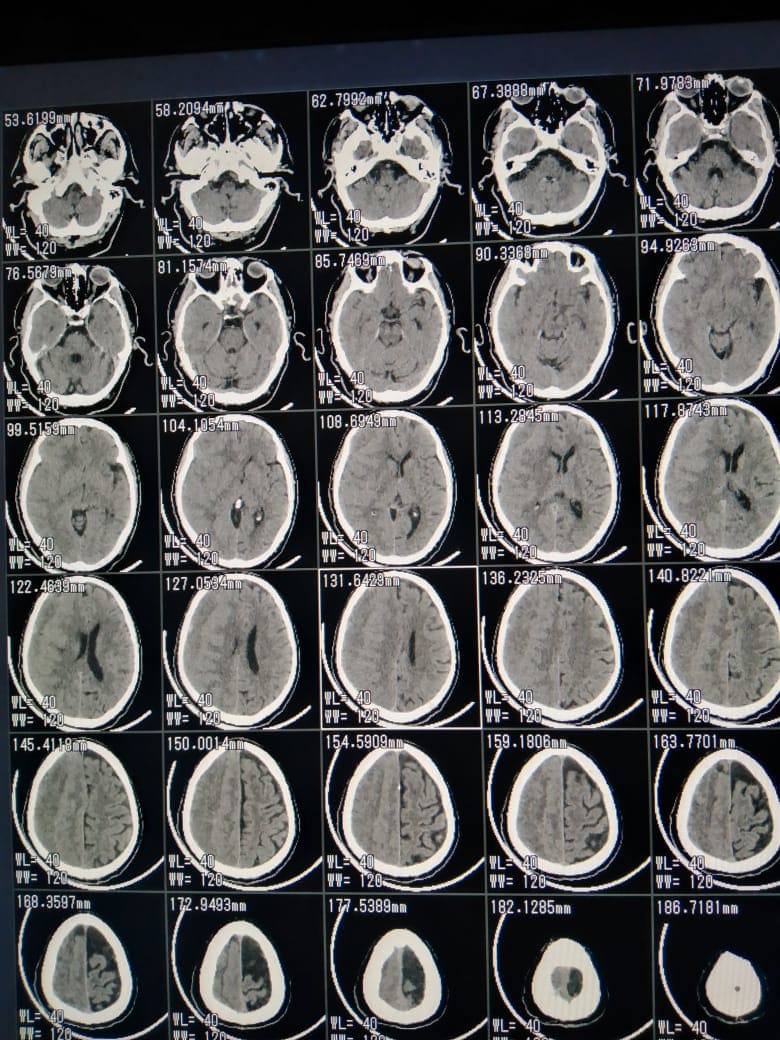

أعلن الدكتور هشام شوقي مسعود وكيل وزارة الصحة بالشرقية بقيام الفريق الطبي بقسم جراحة المخ والأعصاب بمستشفي الزقازيق العام بمشاركة الدكتور وائل المسلمي، والدكتور السيد صباح محمد، والدكتور عماد عبد القادر، وهيئة التمريض بقسم العمليات، قاموا اليوم الجمعة 16 إبريل 2021 بإجراء جراحة دقيقة بالمخ لمسجون يعاني من شلل نصفي تام بالجانب الأيسر نتيجة تجمع دموي بالمخ، وذلك بعد توقيع الكشف الطبي علي المريض وإجراء كافة الفحوصات الطبية والأشعات اللازمة له، والتنسيق بين قطاع السجون ومديرية الشئون الصحية لإجراء الجراحة الدقيقة للمريض، وتوفير كافة أوجه الرعاية الطبية له، وتمت العملية الجراحية بنجاح والحالة الآن مستقرة وتحت الملاحظة الطبية، بإشراف مدير المستشفي.